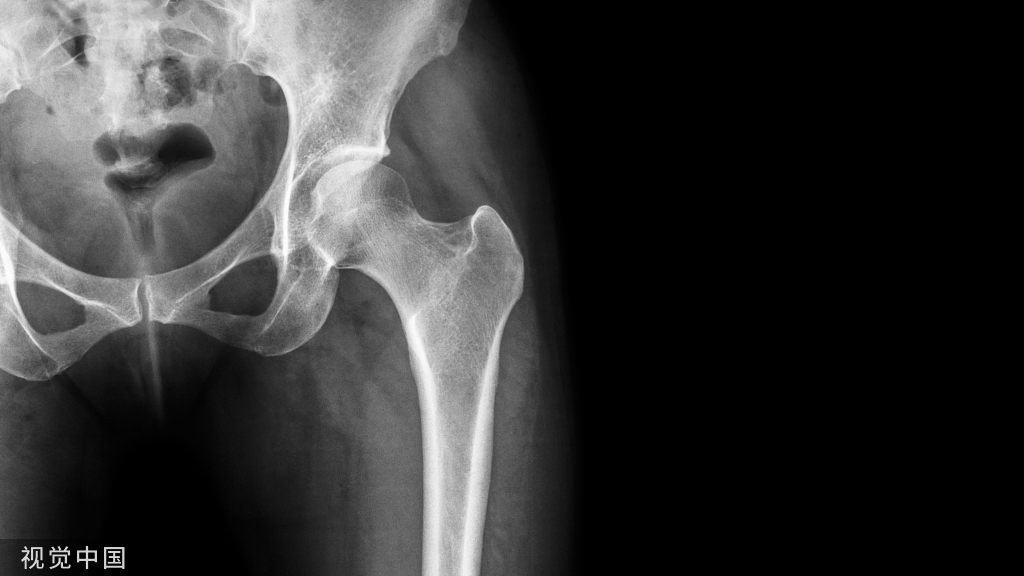

骶椎

在骶椎,通常进钉点为S1关节突外缘纵线与下缘水平切线交点,指向中线或平行于骶髂关节。椎弓根螺钉可以从标准的往前内侧方指向骶骨体或岬部,或者是向前外方进入骶骨翼。

Edwards 发现骶骨螺钉在S1处的植入角度在前内侧25°,或者在骶骨翼外侧成角35°具有最大的拔出力量。

Zindrik 发现在S2椎弓根螺钉固定的力量最弱,如果要提高螺钉的拔出力量应从偏外侧45°角拧入。

Mirkovic 使用椎弓根螺钉通过骶骨前后两面骨皮质以增强固定时,判定S1螺钉放置时易损伤腰骶神经干,髂内静脉和骶髂关节,S1螺钉放置有2个安全区域,其中前内侧最为安全。

骶椎进钉点

- 上 S1关节突外缘的垂线,关节突下缘的水平线交点。

骶椎进钉角度

- 矢状面角度:内倾25度;

- 水平面角度:头倾25-30度,瞄向骶骨岬。

骶椎选螺钉

- 螺钉直径6.5~7.0mm,深度30-35mm